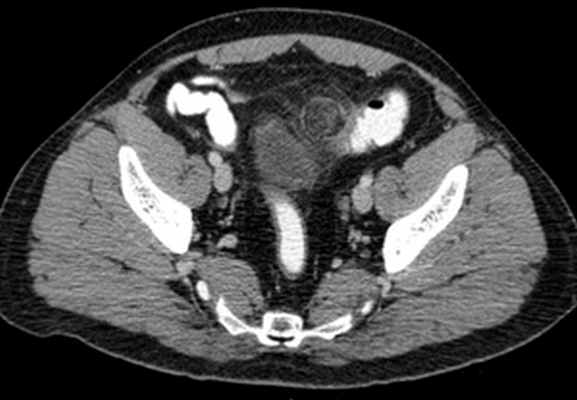

Червеобразный отросток располагается интраперитонеально и имеет обычно хорошо выраженную брыжейку, mesoappendix, в которой проходят сосуды и нервы. Благодаря брыжейке периферическая часть аппендикса обладает значительной подвижностью.

1) тазовое, или нисходящее положение аппендикса, — отросток направлен вниз, в полость малого таза;

2) медиальное положение аппендикса — отросток лежит параллельно подвздошной кишке;

3) латеральное положение аппендикса — отросток находится в правой боковой околоободочной борозде (канале);

4) переднее положение аппендикса — отросток лежит на передней поверхности слепой кишки;

5) восходящее, или подпеченочное положение аппендикса, — отросток направлен верхушкой вверх, нередко до подпеченочного углубления;

6) ретроцекальное положение аппендикса — отросток находится позади слепой кишки.

При таком положении червеобразного отростка возможны два варианта: отросток лежит внутрибрюшинно, тесно прилегая к брюшине задней стенки слепой кишки; отросток лежит забрюшинно, или ретроперитоне-ально. В последнем случае червеобразный отросток располагается в забрюшинной клетчатке, часто достигая места выхода бедренного нерва из межмышечной щели между m. psoas major и m. ileacus.

Этим объясняется возможная иррадиация болей в бедро при аппендиците. Нередко